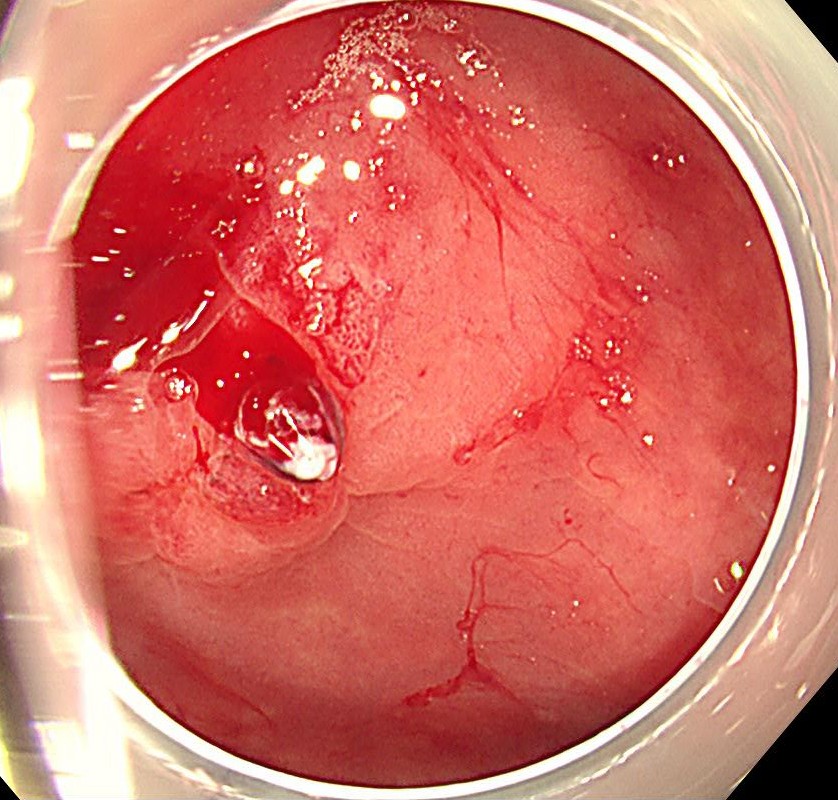

大量下血にて緊急大腸内視鏡施行、直腸Raに噴出性出血を伴う露出血管を認め、Dieulafoy潰瘍と診断しました。

まずはコアグラスパーを用いてソフト凝固60で止血します。